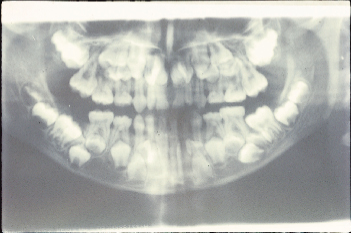

Các loại răng dư Tuberculate ( tạm dịch là dạng củ) có nhiều hơn một chỏm hoặc củ. Hình dạng của nó thường là hình ống và được bao bọc trong ống. Sự hình thành chân răng chậm so với các răng cửa vĩnh viễn. Răng dư Tuberculate thường theo từng cặp và thường nằm trên cung hàm của các răng cửa giữa. Nó hiếm khi nhú lên và thường liên quan đến tình trạng chậm mọc răng cửa (Hình 5 và 6).

Hình 5: Cặp răng dư tuberculate liên quan đến rối loạn mọc răng |

Sự hiện diện răng dư là nguyên nhân phổ biến nhất gây không mọc được răng cửa giữa hàm trên. Nó cũng có thể là nguyên nhân chậm thay răng sữa. Vấn đề thường được chú ý với việc mọc răng cửa bên hàm trên cùng với tình trạng không mọc được một hoặc cả hai răng cửa trung tâm (Hình 5 và 6). Răng dư ở các vị trí khác cũng có thể gây không mọc được các răng lân cận.